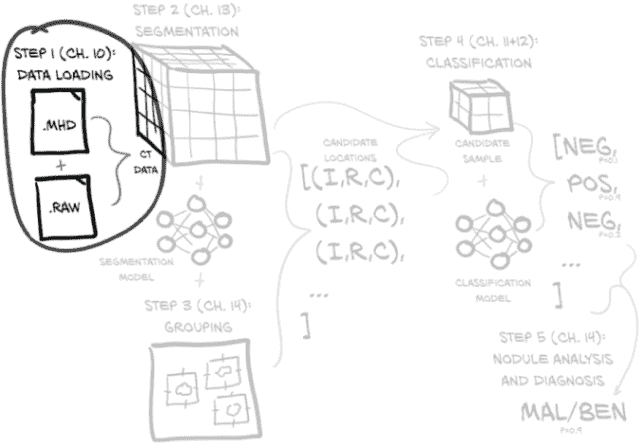

我们在图 9.4 中展示的完整端到端解决方案将加载 CT 数据文件以生成包含完整 3D 扫描的Ct实例,将其与执行分割(标记感兴趣的体素)的模块结合,然后将有趣的体素分组成小块,以寻找候选结节。

图 9.4 完整胸部 CT 扫描并确定患者是否患有恶性肿瘤的端到端过程

结节位置与 CT 体素数据结合,产生结节候选,然后可以由我们的结节分类模型检查它们是否实际上是结节,最终是否是恶性的。后一项任务特别困难,因为恶性可能仅从 CT 成像中无法明显看出,但我们将看看我们能走多远。最后,每个单独的结节分类可以组合成整体患者诊断。

图 9.4 仅描述了在构建和训练所有必要模型后通过系统的最终路径。训练相关模型所需的实际工作将在我们接近实施每个步骤时详细说明。

我们将在第十章中进行第 1 步数据加载工作,第十一章和第十二章将专注于解决分类这些结节的问题。之后,我们将回到第十三章工作于第 2 步(使用分割找到候选肿瘤),然后我们将在第十四章中结束本书的第 2 部分,通过实现第 3 步(分组)和第 5 步(结节分析和诊断)的端到端项目。

让我们在图 9.7 中重复我们的高层概述。

图 9.7 完成全胸 CT 扫描并确定患者是否患有恶性肿瘤的端到端过程